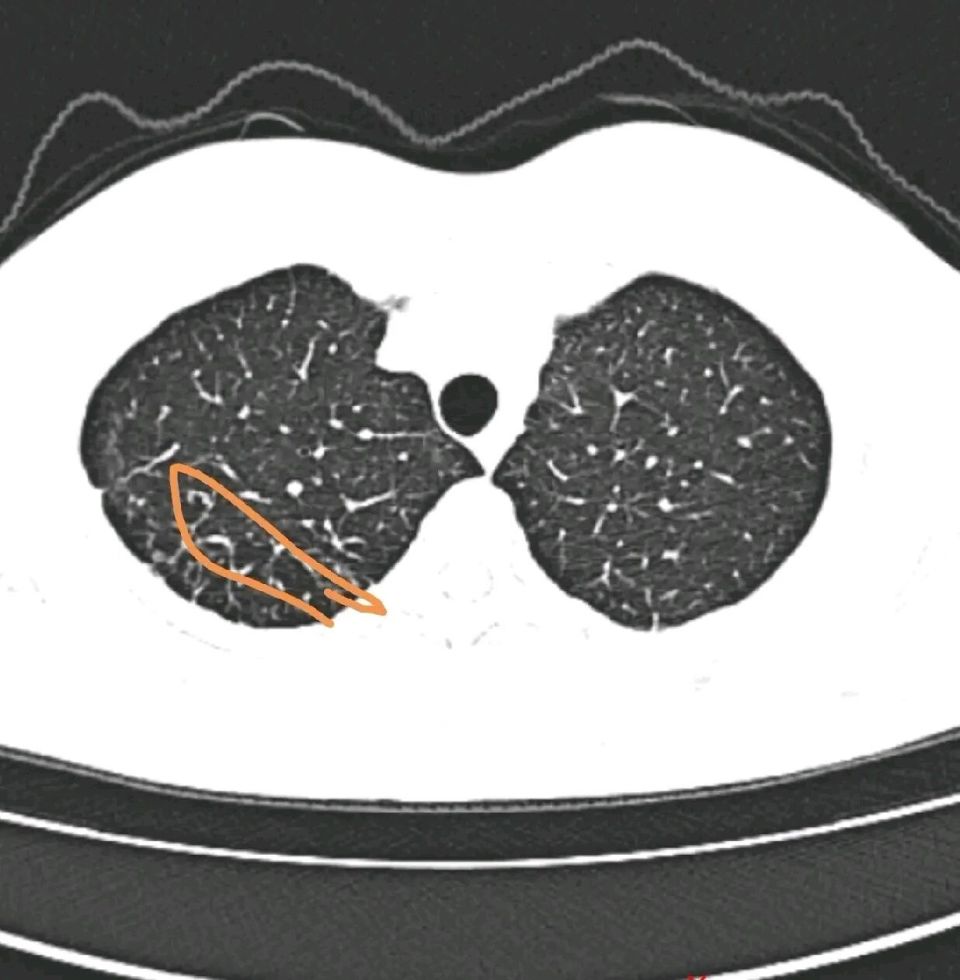

再继续吸烟吸下去,就是第二阶段,肺气肿,肺大泡,这时候肺部长满了大大小小的泡泡,已经属于无法逆转和恢复的阶段,但肺功能还不至于明显的下降,人也不会有气喘或者是体力受限的症状,但如果继续吸烟会进入下一个阶段。

图片